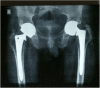

A plain radiograph at the time of presentation, showing bilateral large uncemented metal-on-metal total hip arthroplasty, with trunnion fracture on the left hip